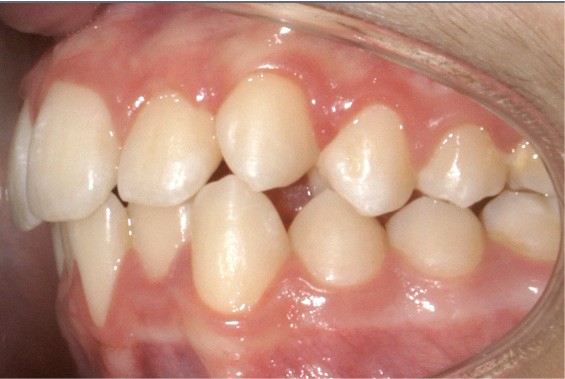

Examen endo-buccal (fig. 2a-e)

Au niveau des relations occlusales, on observe une Classe I molaire associée à une Classe II canine de 2 mm à droite ainsi qu’une Classe II molaire de 1 mm et une Classe II canine de 3 mm à gauche. Le surplomb est normal.

Dans le sens transversal, l’occlusion des secteurs latéraux est correcte mais on constate une discordance des médianes incisives liée à la déviation de la médiane maxillaire vers la droite et à celle de la médiane incisive mandibulaire vers la gauche.

Le recouvrement est de 2 mm.